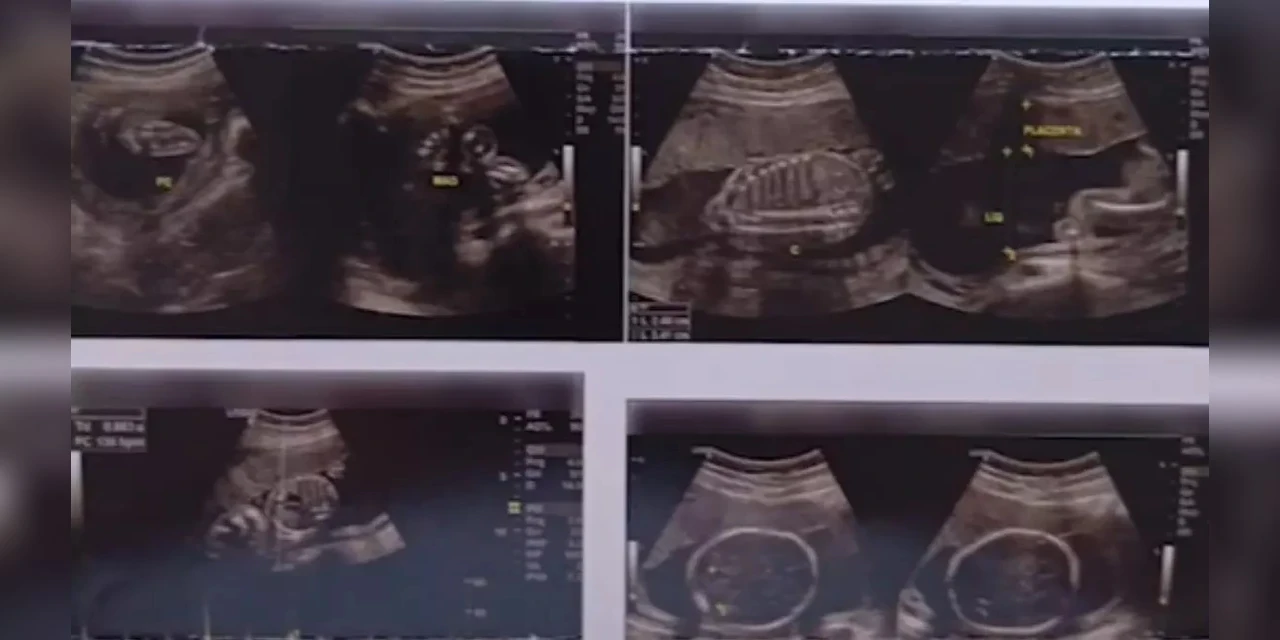

Homem faz ultrassom e recebe diagnóstico de gravidez no Paraná

Paciente se queixava de dores abdominais e foi supreendido pelas imagens reveladas no exame

(Foto: Reprodução/RICtv)

Um homem residente no estado do Paraná realizou um exame de ultrassom, à princípio para identificar a ocorrência de duas hérnias, mas foi surpreendido com um diagnóstico de gravidez, sendo possível ver o bebê nas imagens reveladas pelo procedimento.

“Fui fazer um ultrassom para ver duas hérnias, que é caso de operação. Só que chegou o resultado do exame e diz que eu estou grávido, vou ter um filho. No exame consta meu nome, tudo certinho, estou grávido”, disse o homem não identificado em áudio encaminhado pelo aplicativo WhatsApp.

Segundo informações do Cidade Alerta, o fato aconteceu por conta de uma troca das imagens dos exames de ultrassom dele com o de uma mulher, que de fato, estava grávida.